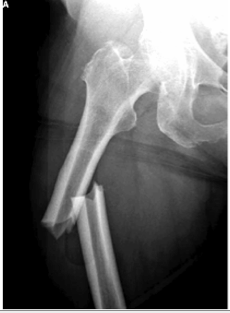

- Shortly after arrival the following x-ray is taken

- This x-ray is interpreted as a right femoral shaft fracture